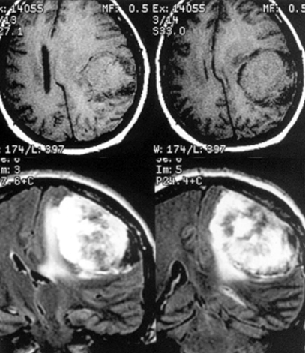

К конвекситальным относят менингиомы, исходящие из ТМО наружной поверхности мозга, не связанные с верхним сагиттальным синусом и его боковыми лакунами (рис. 1). Они составляют 23% внутричерепных менингиом и делятся по анатомическим областям на лобные, теменные, височные и затылочные. Изредка встречаются внутрикостные (интраоссальные, оссальные) и эктопические менингиомы.

Рисунок 1. Конвекситальная менингиома левой теменной области. МРТ, Т1-взвешенные изображения до (вверху) и после (внизу) контрастного усиления. Несмотря на большие размеры, опухоль не имеет отношения к верхнему сагиттальному синусу